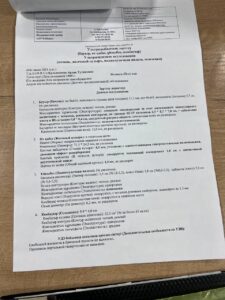

Кульжанова Ардак Туленовна 31 декабря 1960 года рождения, в марте 2024 с кровотечением поступила в ТОО » Национальный научный онкологический центр», где был выставлен диагноз » эхинококкоз печени».

От проведения операционного вмешательства отказалась ( две кисты в печени).

Обратилась к Евгению Хынчановичу в клинику «Юджина» г. Алматы. Собрала необходимую информацию по лечению, ведению больных в клинике, а также их излечении.

С марта по ноябрь 2024 года принимала противопаразитарные, иммуностимулирующие и восстанавливающие функции внутренних органов препараты, в купе с соблюдением необходимой диеты и ходьбы. На сегодня 21 ноября 2024 года, чувствую себя отлично ( самочувствие хорошее, энергия отличная, посветлела и исчезают пигментные пятна на лице и ТД).

На УЗИ от 06.11.2024 наблюдается положительная динамика.